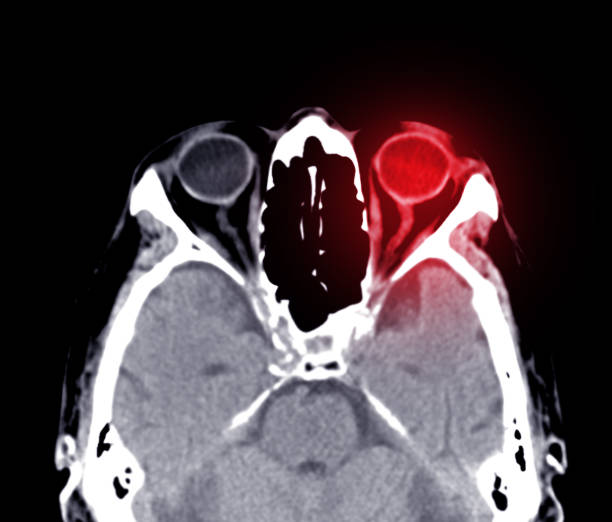

결막염 합병증

결막염 증상은 일반적으로 약물을 사용하면 시간이 지남에 따라 자연치료가 가능할 정도로 크게 걱정하지 않아도 됩니다. 다만, 2차 세균 감염이나 각막염 등의 합병증에 주의를 기울여야 하며, 증상이 완치될 때까지 후속 치료를 하는 것이 좋다. 치료하지 않거나 마음대로 중단하면 결막 염증으로 흉터가 남고 시야가 흐려질 수 있으며 결막 염증으로 눈물샘 세포가 손상되어 합병증으로 안구 건조증이 생길 수 있습니다.